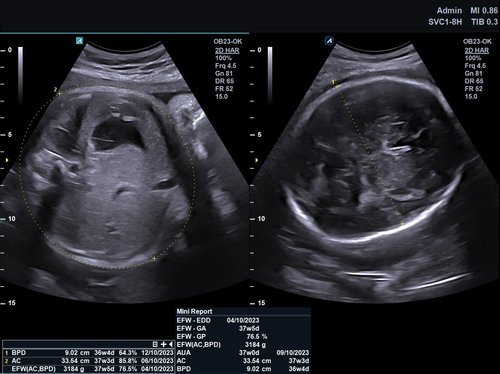

• SC1-7H (1-7 MHz) für Ultraschalluntersuchungen in den Bereichen Abdomen, Geburtshilfe, Gynäkologie, Urologie, Pädiatrie, EM

• SVC1-8H (1-8 MHz) für Ultraschalluntersuchungen in Bereichen Abdomen, Geburtshilfe, Gynäkologie, Urologie, Pädiatrie, EM

• Automatisierte Messungen und Workflow (optional)